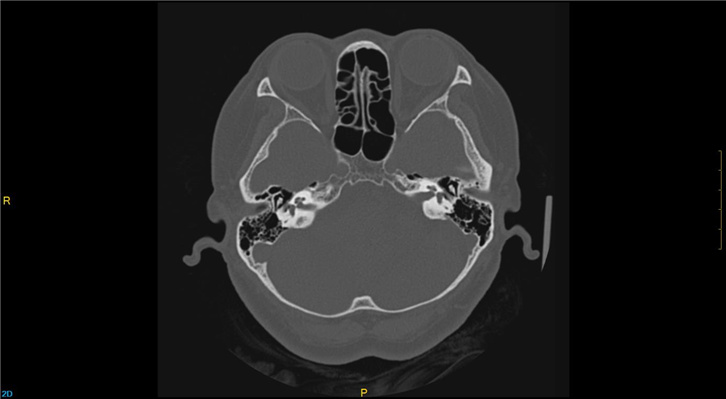

Care 240°器官保护扫描模式,240°数据成像避免了眼球、甲状腺、乳腺等射线敏感器官的直接照射,使患者健康得到保护;